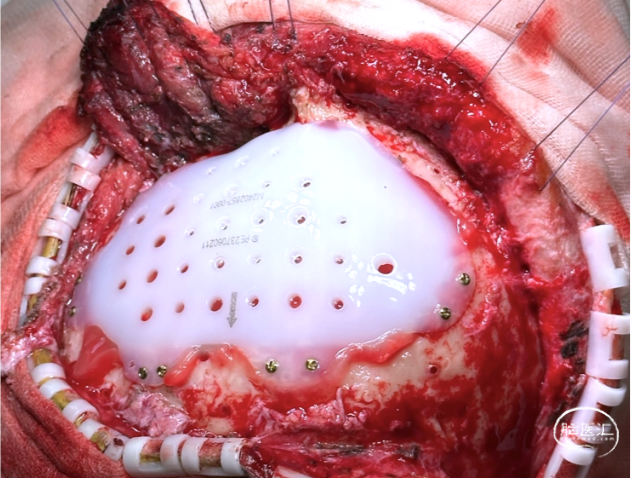

1. 去除钛网,重新行颅骨修补,修补材料为3D打印超高分子量聚乙烯(UHMWPE)网板。

2. 新修补材料植入颞肌下,嵌入骨窗内,恢复正常解剖层次,恢复容貌外观。

修补材料设计方案:UHMWPE网板,标准弧度设计,厚度4mm;与颅骨间隙0.8-1mm;预留孔颞部孔径4mm,其余3mm;采用全覆盖式,翼状结构固定。

手术过程